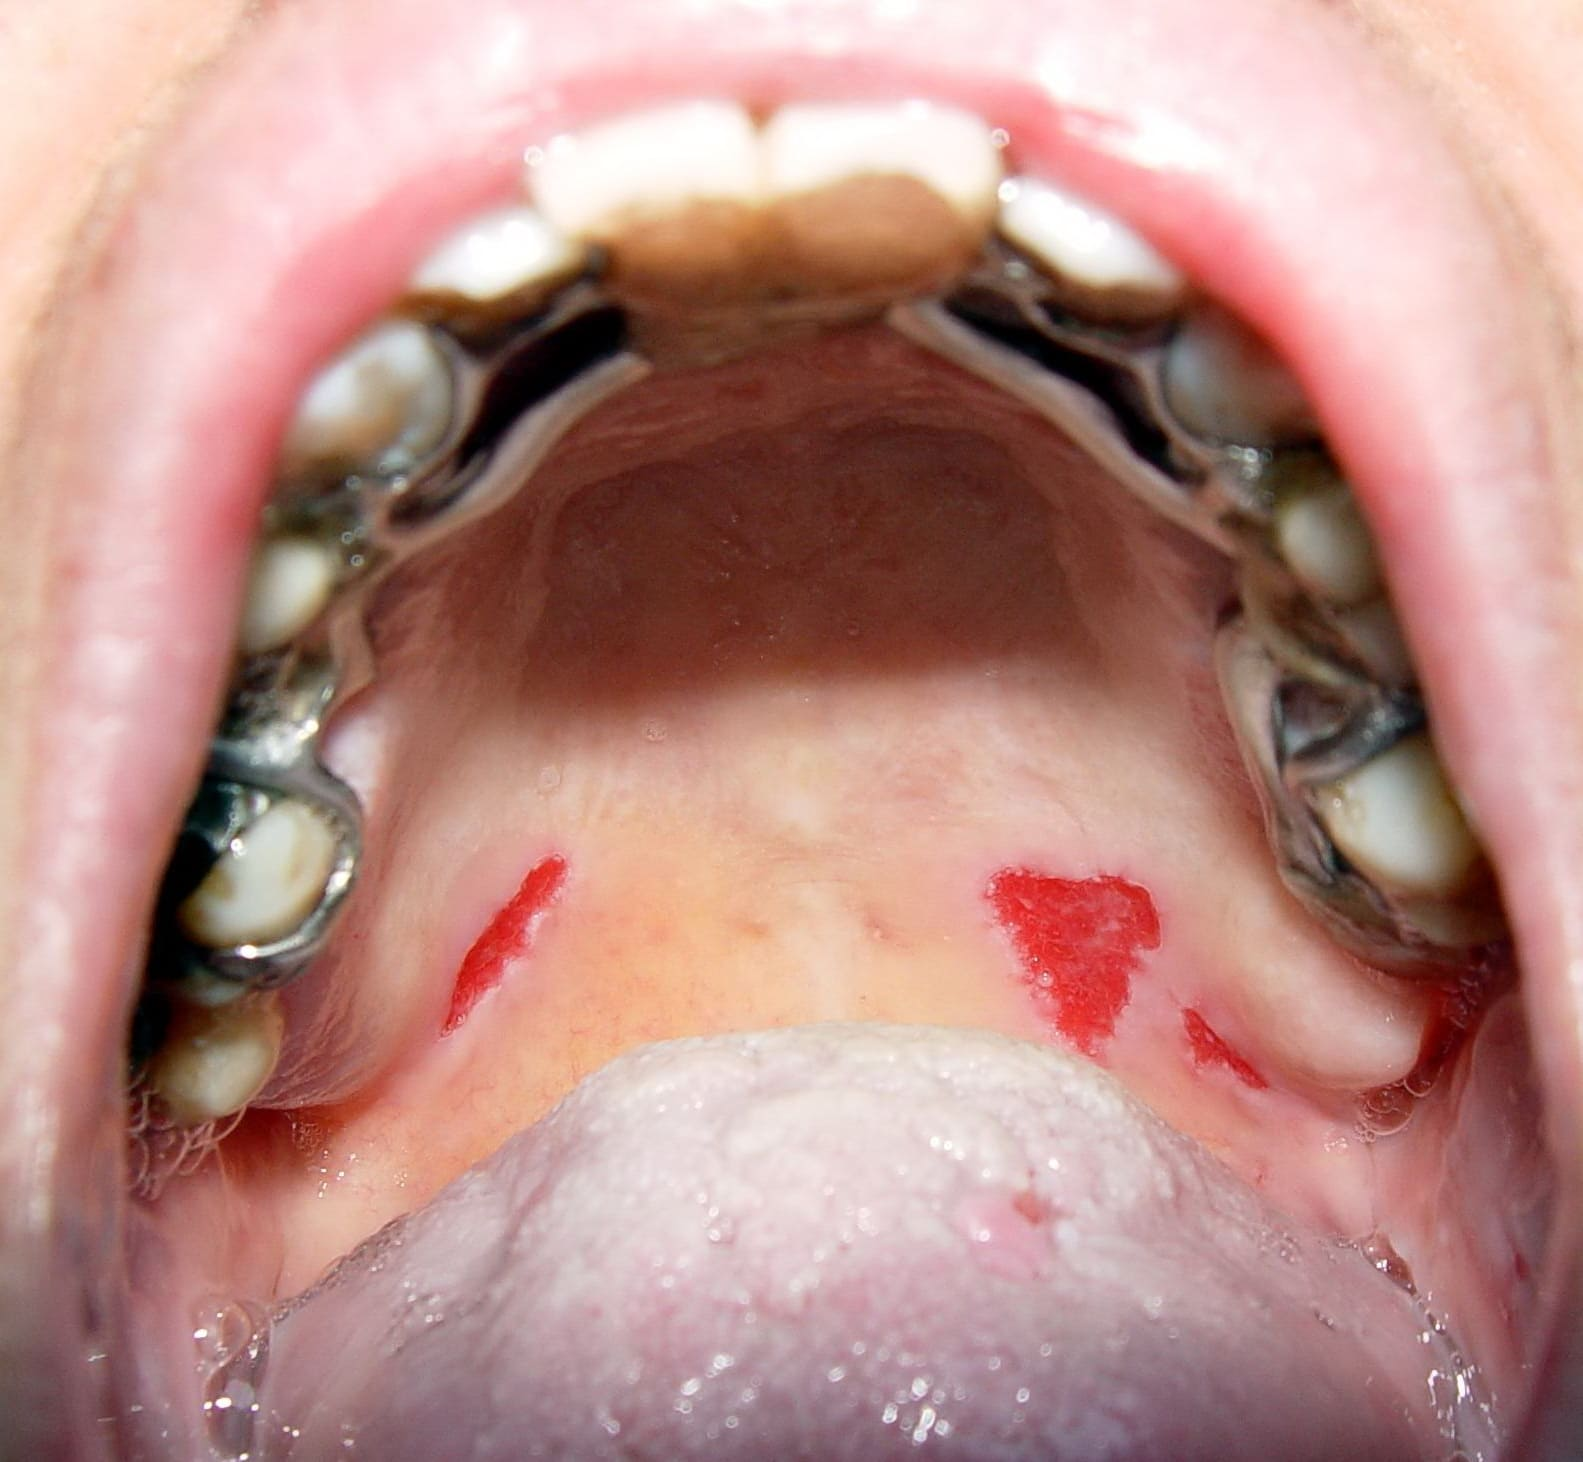

Pemphigis Vulgaris =الفقاع الشائع